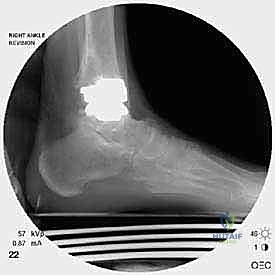

خطوات جراحة مراجعة مفصل الكاحل (Agility) بالتفصيل

تعتبر غرفة العمليات ساحة لإظهار البراعة الجراحية. عملية المراجعة تستغرق عادة من 3 إلى 5 ساعات وتتم عبر الخطوات المعقدة التالية:

الخطوة الخامسة: تركيب المفصل الجديد أو الدمج

يتم إدخال المفصل الجديد المخصص للمراجعة، والذي يحتوي غالباً على سيقان (Stems) تدخل عميقاً في عظمة الساق وعظمة الكاحل لضمان الثبات الميكانيكي. في حال وجود كسور في الكعب، يتم تثبيتها في هذه المرحلة.

الخطوة السادسة: الإغلاق التجميلي

يتم خياطة الأربطة والأنسجة الرخوة والجلد بطرق تجميلية دقيقة لتقليل الندبات وسرعة الالتئام، ثم توضع القدم في جبيرة خلفية واقية.